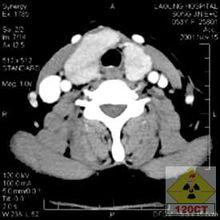

雙期增強掃描雙期增強掃描雙期增強掃描是指利用螺旋CT掃描速度快的優點,在一次靜脈注射對比劑後根據檢查器官的血供特點,分別於強化的不同時期對檢查的器官進行兩次或多次完整的螺旋掃描。

雙期增強掃描 - 方法 先平掃,設定增強掃描的範圍以及兩次或多掃描開始時間,掃描參數與平掃相同,經靜脈用電動壓力注射器注入對比劑80ml~100ml,3ml~4ml/s,對比劑注射完後與掃描開始時間同步。

25s~30s肝臟動脈期肝硬化患者開始掃描時間要晚一些

60s~70s肝臟門靜脈期

120s肝實質平衡期 胰腺 25s~30s胰腺動脈期

60s~70s胰腺實質期

30s~35s腎皮質期

70s腎實質期